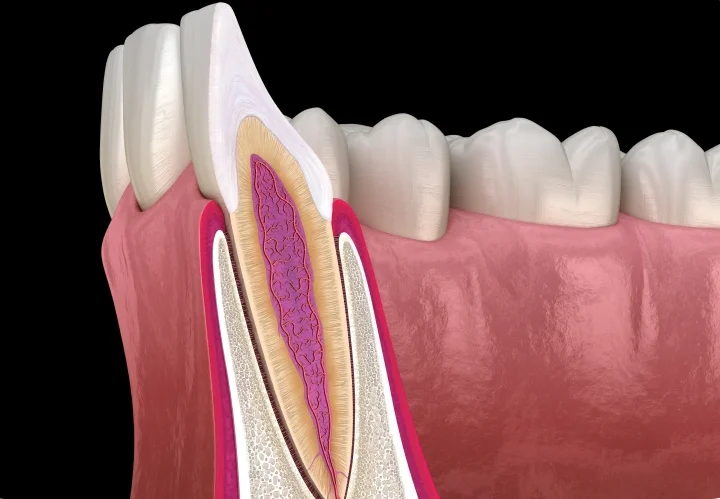

Chirurgie parodontale

La chirurgie parodontale traite les maladies avancées des gencives et de l’os alvéolaire, telles que la parodontite sévère. Elle permet de stabiliser les dents, de réduire les poches parodontales et de restaurer un environnement sain pour la dentition.

Les techniques comprennent :

- Surfaçage radiculaire profond pour nettoyer les racines et éliminer les bactéries.

- Résection de poches parodontales pour réduire l’inflammation et favoriser la cicatrisation.

- Reconstruction tissulaire pour régénérer l’os et les gencives lorsque nécessaire.

Résection apicale

La résection apicale est une intervention chirurgicale visant à retirer l’extrémité infectée de la racine d’une dent tout en conservant la dent elle-même. Elle est indiquée lorsque les traitements endodontiques classiques ne suffisent pas.

Les étapes comprennent :

- Anesthésie locale pour un confort optimal.

- Accès chirurgical à la racine infectée et retrait de l’infection.

- Sutures et cicatrisation pour préserver la gencive et l’os autour de la dent.

Cette procédure permet de préserver la dent naturelle, protéger l’os alvéolaire et prévenir la propagation de l’infection. Le suivi post-opératoire inclut des contrôles réguliers, une hygiène adaptée et éventuellement un ajustement de la prothèse ou de l’implant futur.